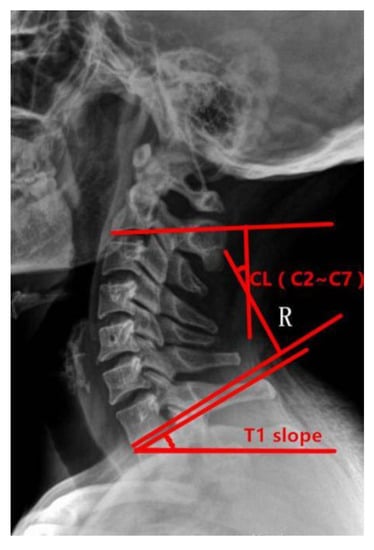

Preoperative and postoperative cervical lordosis: neutral lateral radiographs of the cervical spine were taken before, after, and during the follow-up, and the cervical lordosis angle was measured by a computer (Cobb’s method: tangents are made from the lower edges of C2 and C7, respectively, and the angle between the tangents is used as the value of the cervical curvature) (Figure 1, Figure 2 and Figure 3). Differences in preoperative and postoperative cervical lordosis were compared as loss of lordosis. The cervical disability index (NDI) and visual analog scale (VAS) were calculated before and after surgery. All patients were divided into two groups, A and B, according to a mean value of T1s = 23.54°, where group A consisted of cases with T1S > 23.54° and group B consisted of cases with T1s < 23.54. The postoperative change in cervical lordosis was determined by comparing the preoperative and postoperative C2–C7 Cobb angles. Then, the difference in cervical lordosis was measured before and after the operation, and its correlation with preoperative T1s was assessed. The preoperative cervical lordosis and cervical curvature changes in the two groups were statistically compared.

Figure 2.

Cobb angle of cervical curvature. The angle formed by the parallel line of C2 lower endplate and C7 lower endplate represents the curvature of cervical vertebra.